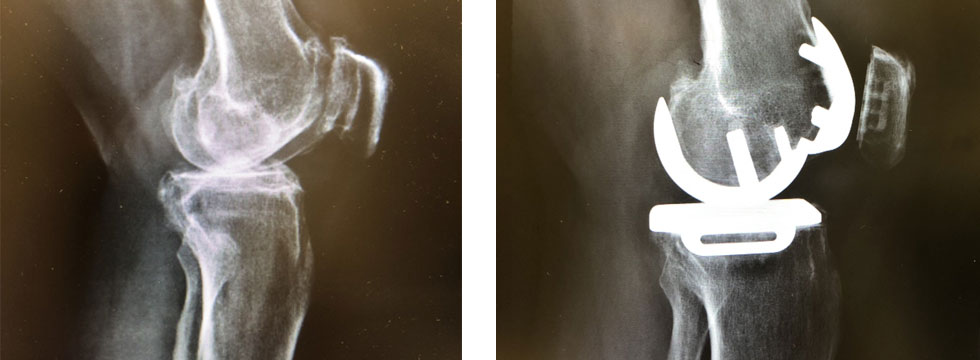

范智豪醫生表示,該院在12年前已引入「局部膝關節置換術」,技術保留了病人完整的關節、骨骼及十字韌帶,傷口較小,病人在術後的活動能力可更好,最快一天已可出院。局部人工關節的壽命亦與全膝關節的假體相若,約有15年。院方在去年1月更引進新款設計的人工關節,每年只會磨蝕0.01至0.02毫米,遠較舊式假體每年磨蝕0.13至0.15毫米為好。他透露,在引入新式設計前,只有較輕微的病人可以做局部膝關節置換,「一百人中只有三、四人,現在有兩、三成人都可以。」那打素醫院在去年首8個月就完成77宗局部膝關節置換手術,是本港最多,惟該院目前仍有1,100宗輪候膝關節及髖關節的個案,當中膝關節佔約八、九成。